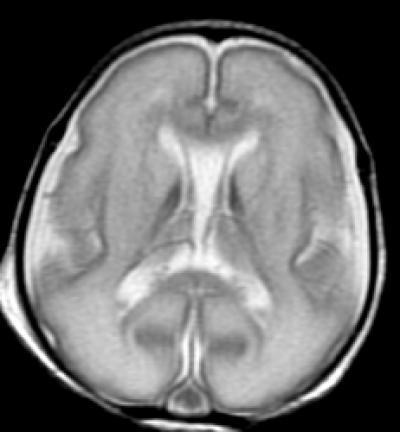

This image shows anatomy (MRI) -- at term.

(Photo Credit: Radiological Society of North America)